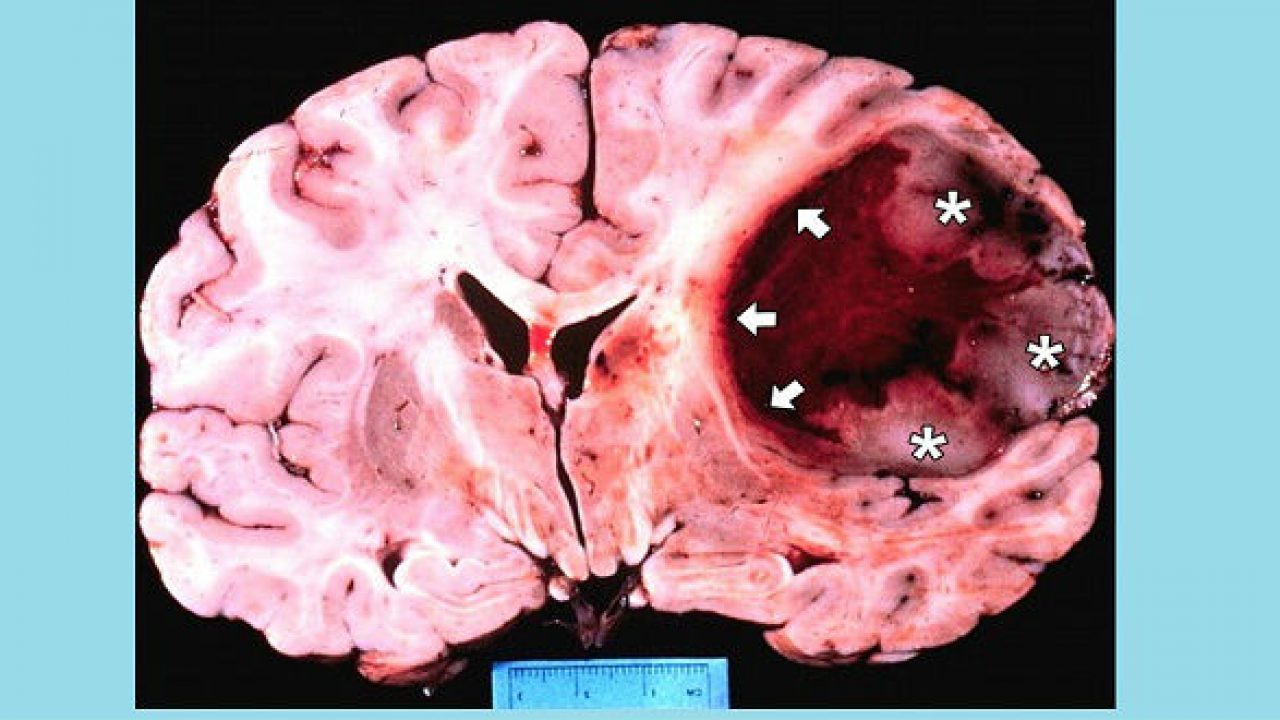

U nguyên bào thần kinh là một loại khối u ác tính xuất hiện ở trẻ em và người lớn. Đây là những khối u chưa trưởng thành, không biệt hóa. U nguyên bào thần kinh là những khối u trung gian và u hạch là những biến thể lành tính của u nguyên bào thần kinh; gọi chung là u mào thần kinh. Các triệu chứng lâm sàng của bệnh u nguyên bào thần kinh phụ thuộc vào vị trí nguyên phát của u và hình thức di căn của bệnh. Các triệu chứng phổ biến nhất là đau bụng, cảm giác khó chịu, dễ kích thích, chán ăn và cảm giác no do khối u ở bụng.

Điều trị u nguyên bào thần kinh đệm

Cách điều trị u nguyên bào thần kinh đệm phụ thuộc vào giai đoạn của bệnh và tình trạng sức khỏe của bệnh nhân. Tuy nhiên, phương pháp điều trị chính của u nguyên bào thần kinh đệm đa dạng là phẫu thuật, sau đó là xạ trị và hoá trị. Mục tiêu chính của phẫu thuật là loại bỏ khối u càng nhiều càng tốt mà không làm tổn thương các mô não bình thường xung quanh cần thiết cho các chức năng thần kinh (như chức năng vận động, ngôn ngữ và di chuyển). Mặc dù mục tiêu của hoá trị là kiểm soát khối u lâu dài, nó chỉ làm được điều này cho khoảng 20% bệnh nhân. Quyết định thay đổi thuốc hoá trị khác cho khối u tái phát thường dựa trên tổng hợp kết quả của các xét nghiệm và tình trạng sức khỏe của bệnh nhân.